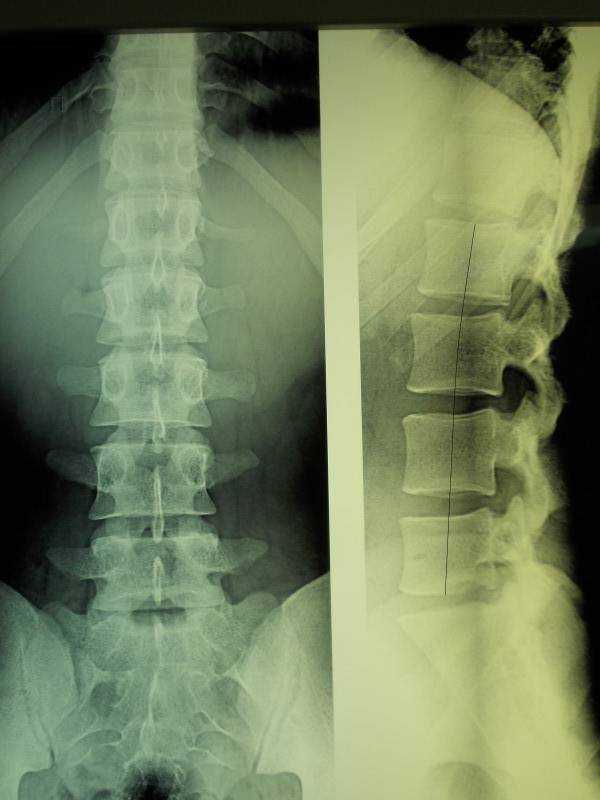

Рентген поясницы: анатомические особенности и медицинские исследования